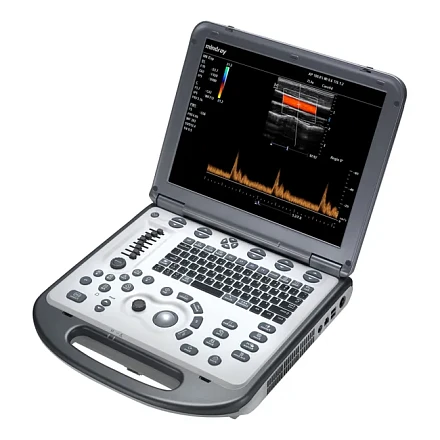

УЗИ аппарат Mindray M6 портативный

Характеристики

- M6 основной блок

- 15" монитор высокого разрешения

- Режимы сканирования:B/M/CFM/PDI/Направленный PDI/PW/Цветной M-режим

- Импульсно-волновой допплер PW (включая режим высокой частоты повторения импульсов HPRF)

- iBeam™ - многолучевое сложносоставное сканирование

- iClear™ - адаптивный алгоритм подавления зернистости

- PSH™ - Гармоника с фазовой инверсией

- iTouch™ - автоматическая оптимизация изображений

- iZoom™ - увеличение изображения во весь экран

- HR Flow - Режим отображения кровотока с высоким пространственным разрешением

- iScanhelper -Встроенный атлас ультразвуковых исследований

- 1T твердотельный жесткий диск и База данных пациентов iStation™

- Разъем S-Video и 2.0 USB порты

- Блок питания и литий-ионная батарея

- Кейс (чемодан) для транспортировки